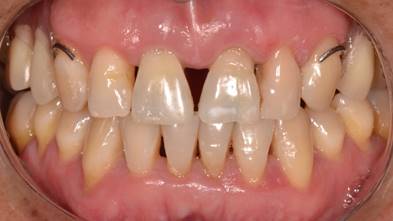

Hombre de 42 años, sistémicamente sano, asiste al Departamento de Implantología de la Universidad de Los Andes. El examen clínico y radiográfico evidenció desdentamiento parcial superior e inferior. La evaluación periodontal mostró una periodontitis crónica generalizada. Se confirmaron fracturas asintomáticas de ambos incisivos centrales superiores en el tercio medio radicular, con leve desplazamiento coronal y movilidad clase II (Fig. 1). La primera etapa terapéutica consistió en la realización de tratamiento periodontal e instalación de una prótesis parcial removible. Se indicó la toma de un examen Cone Beam CT.

Clínicamente no se visualizaron signos y/o síntomas que denotaran fracaso funcional o estético de la rehabilitación protésica al año de seguimiento, como se evidencian en (Fig. 5 e Img 3)